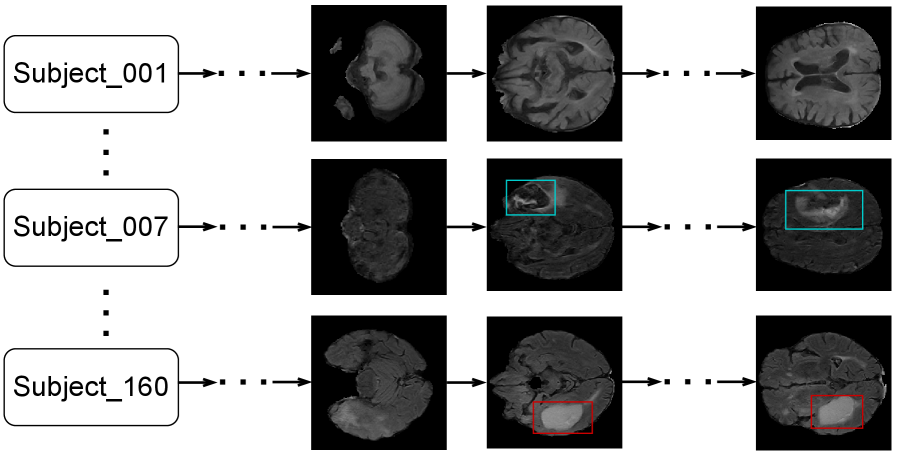

ReBrain adopts this retrieval-augmented strategy. Its performance upper bound in reconstructing complete MRI volumes is inherently limited by the prior knowledge stored in the database. Therefore, constructing a comprehensive and diverse knowledge base is crucial to increase the likelihood of successful retrieval, enabling structurally accurate control of the BBDM during MRI generation. Given the structural and physiological similarities among human brains and the relatively small individual variations, it is generally feasible to build such a knowledge base using training data or additional homologous datasets. An illustration of the knowledge base structure is shown in Figure 3.

Next, we describe how to train the retrieval model. Since cross-subject similarity labels are not necessarily available, it is unclear which brain scans from different subjects are similar, so we adopt an intra-subject training strategy. Specifically, through training on adjacent slices within each subject, the retrieval model learns to capture the shared anatomical structure of human brains, enabling it to retrieve similar slices across different subjects. To implement this, we use a pretrained Vision Transformer (ViT) [Dosovitskiy_2020_ViT] and fine-tune it using a contrastive learning loss. We consider each brain volume as multiple slices with defined spatial positions. For any slice at position , we compute the similarity between its embedding and those of slices within a local neighborhood, specifically at positions . is trained to assign higher similarity scores to slices close in position, reflecting anatomical continuity. Initially, the similarity computation was performed bidirectionally, considering both and relative to . However, we observed redundancy: the similarity between and is effectively optimized when processing position against . Therefore, a unidirectional contrastive loss suffices, reducing complexity while maintaining performance.